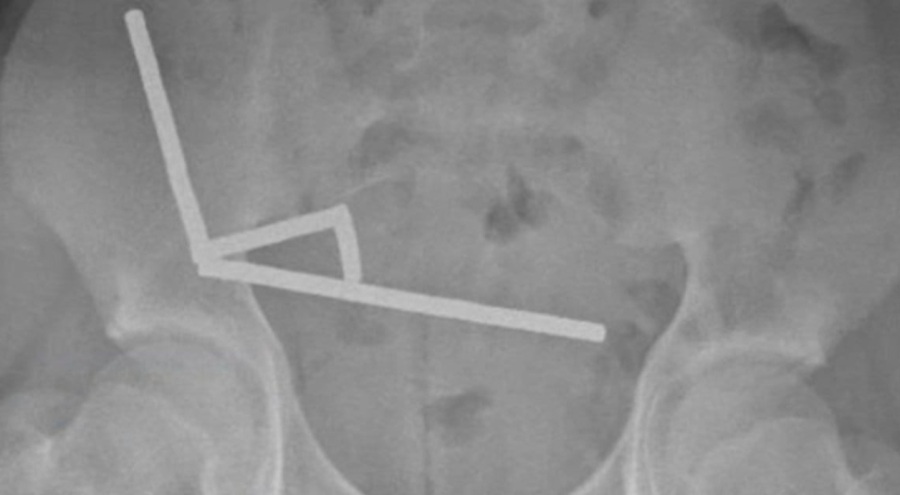

Yeni Zelanda'da yaşanan tıbbi vakada, 13 yaşındaki bir çocuğun yuttuğu yaklaşık 100 mini neodyum mıknatıs, bağırsak dokusunda ciddi hasara yol açtı. "New Zealand Medical Journal" dergisinde yayımlanan vaka raporuna göre, günler süren karın ağrısı şikayetiyle hastaneye getirilen çocuğun röntgen görüntülerinde, karnının sağ alt bölgesinde birbirine yapışmış metal yığınları tespit edildi.